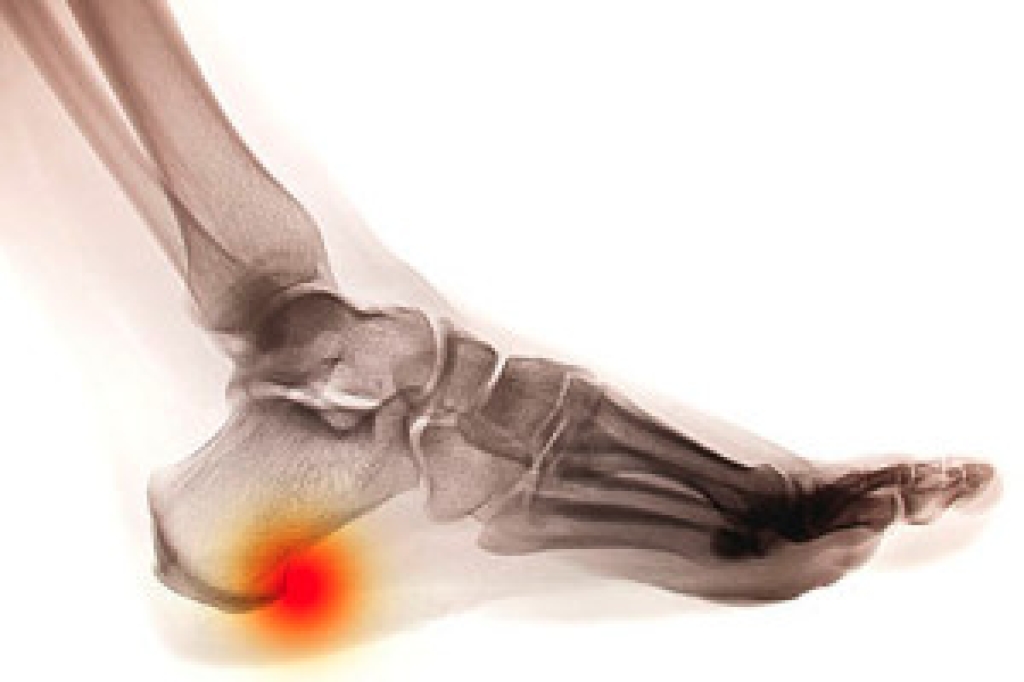

As small as a heel spur is, it can bring severe pain and discomfort to the patient. It is a bony protrusion that may be pointed and is found underneath the heel. It is a calcium build-up, and can gradually come from wearing shoes that do not fit correctly. Many times a heel spur may be misdiagnosed as plantar fasciitis, which is another condition that affects the heel. A diagnosis consists of undergoing an examination that can determine how tender the heel is, in addition to possibly having an X-ray taken. There are patients who find mild relief when anti-inflammatory medications are taken, despite being a temporary fix. Another option that may be considered are custom-made orthotics, and these may help to diminish pressure on the Achilles tendon. If you have heel pain, it is strongly suggested that a podiatrist is consulted who can determine what the cause is, and offer correct treatment options.

Heel spurs are formed by calcium deposits on the back of the foot where the heel is. This can also be caused by small fragments of bone breaking off one section of the foot, attaching onto the back of the foot. Heel spurs can also be bone growth on the back of the foot and may grow in the direction of the arch of the foot.